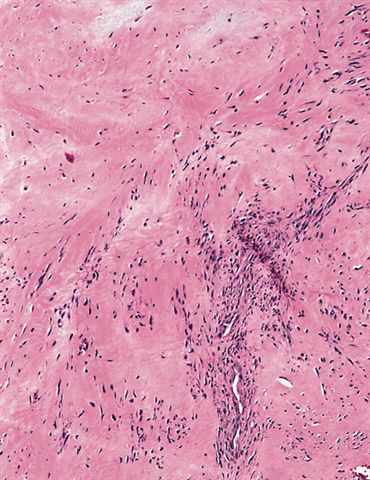

Microscopic (histologic) description

- Well circumscribed tumor of variable cellularity

- Cellularity mostly higher at tumor edges

- Bland spindle cells in a collagenous background

- Tumor has characteristic thin walled slit-like vessels

- Degenerative changes like myxoid / cystic change, osseous / chondroid metaplasia can be seen

- Mitotically inactive

- Necrosis not present

Microscopic (histologic) images

Contributed by Nasir Ud Din, M.B.B.S.

AFIP images